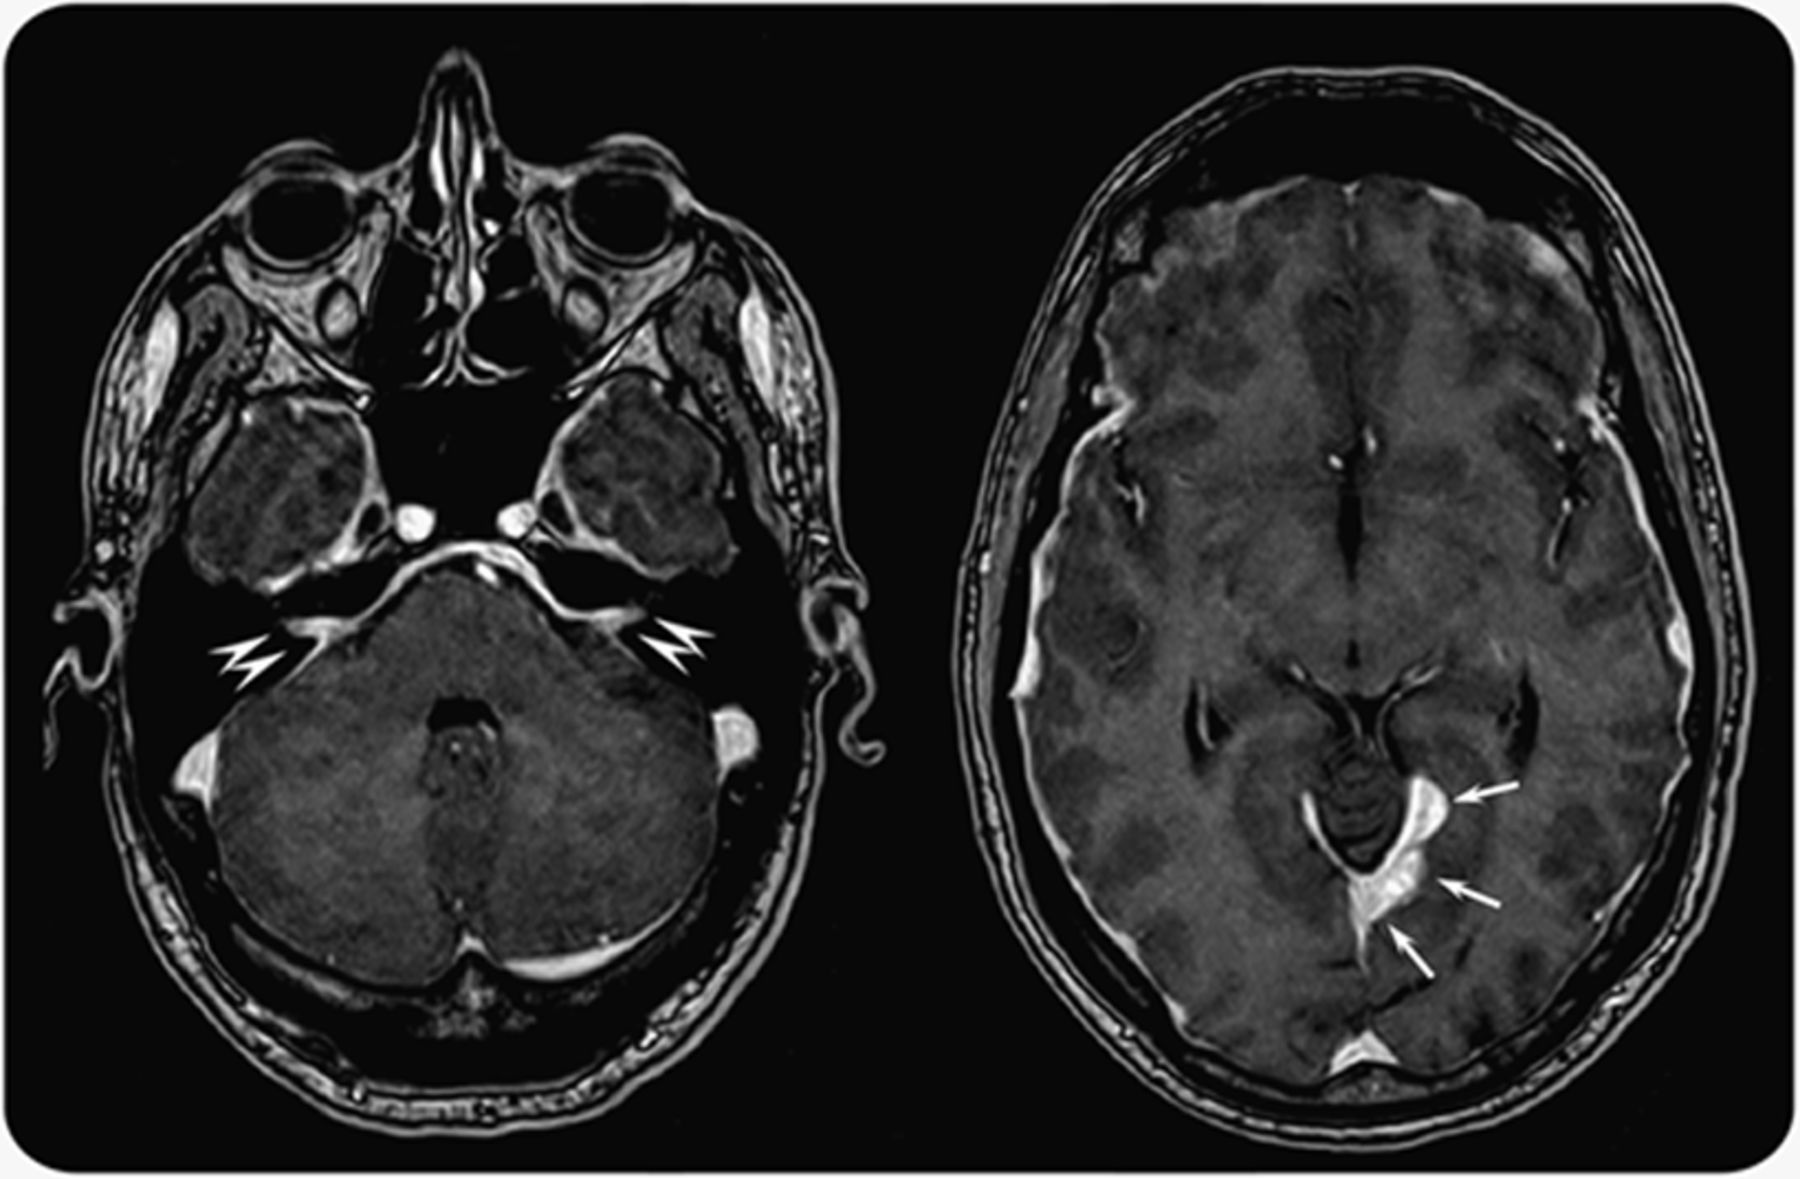

图2

组织病理结果

(A)部分脑膜和浆细胞浸润,苏木精和伊红())200×。(B)更强的放大显示浆细胞不典型特征,他走时400×。(C)积极的浆细胞,CD138染色,400×。(D)积极的浆细胞,免疫球蛋白G4染色(见箭头),400×。